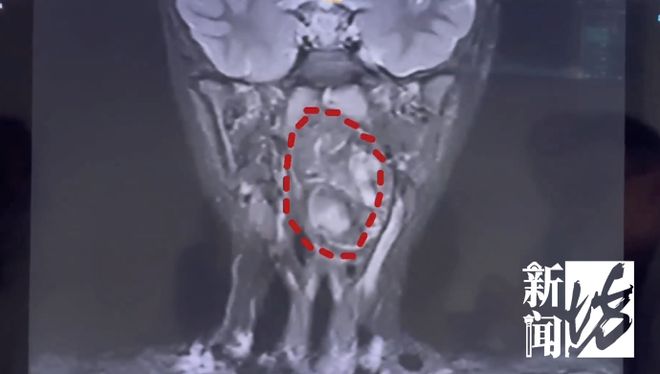

图为拍的CT片子

陈超副主任解释说:“我们可以看到它有脂肪和软骨组织,像是一个未完成的人类胚胎,另一个则可能在咽旁间隙发育成了这样的畸形肿块。”

陈超副主任表示:“六岁儿童的口咽腔大约为8厘米左右,而这个孩子的肿瘤已经高达6.5厘米以上,几乎完全占据了他的气道。”